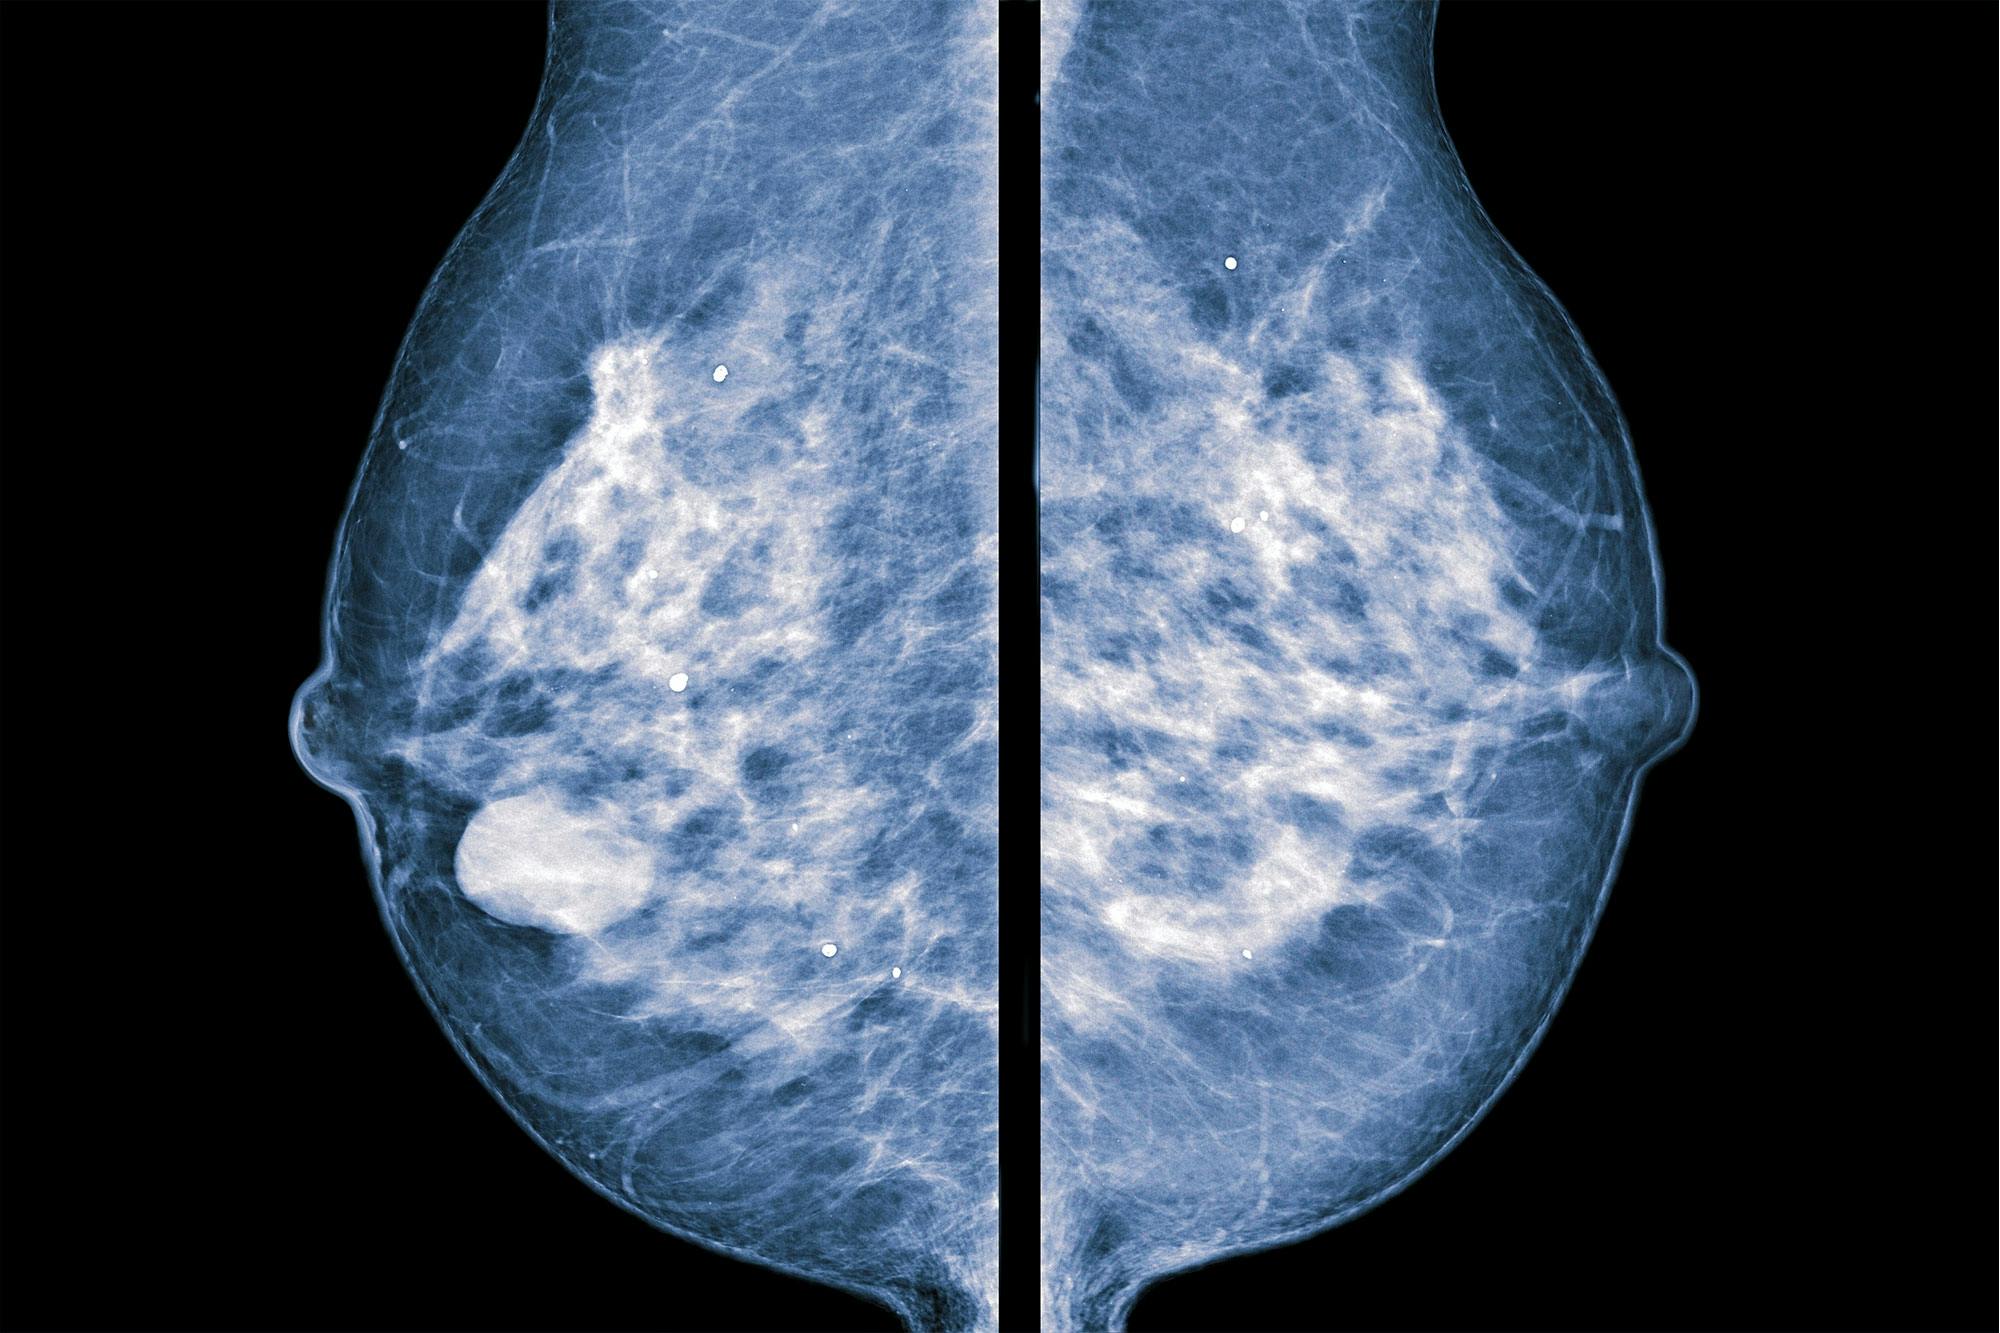

UNDERSØGELSE AF BRYSTKRÆFT Ved mammografi presses brystet fast mellem to glasplader, hvor brystet så undersøges med røntgen- og/eller ultralydsundersøgelse. Der vil man kunne se, om der er en knude. Til venstre ses et bryst med en knude, og til højre et normalt bryst.